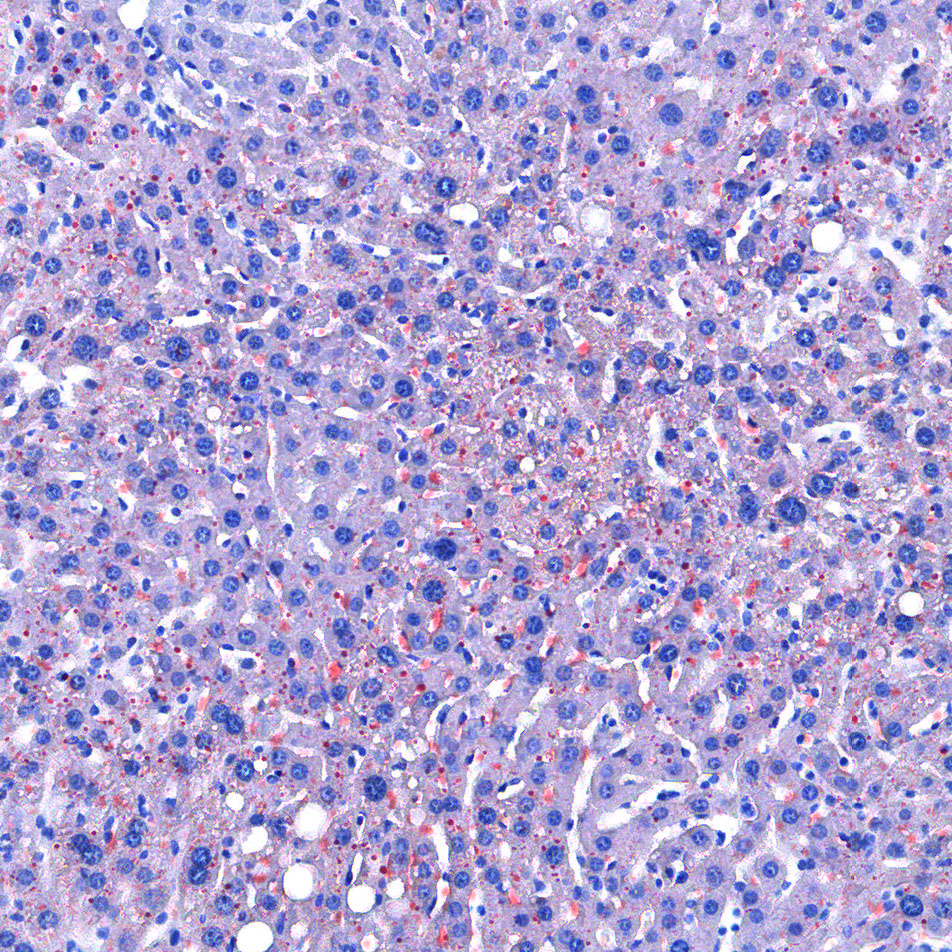

油红O染色

油红O对脂滴的染色机制一般认为是物理学上的溶液作用或吸附作用,借溶液作用使脂质染色,即油红O先溶于60%异丙醇中,然后切片浸入油红O染液中时,油红O在组织脂质的溶解度较60%异丙醇中的溶解度高,所以在染色时油红O从60%异丙醇中转移入脂质中使脂滴显示红色。

实验结果展示:

<油红O-肝>